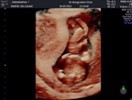

ชัดจ้า ซาวตอน 12w6d